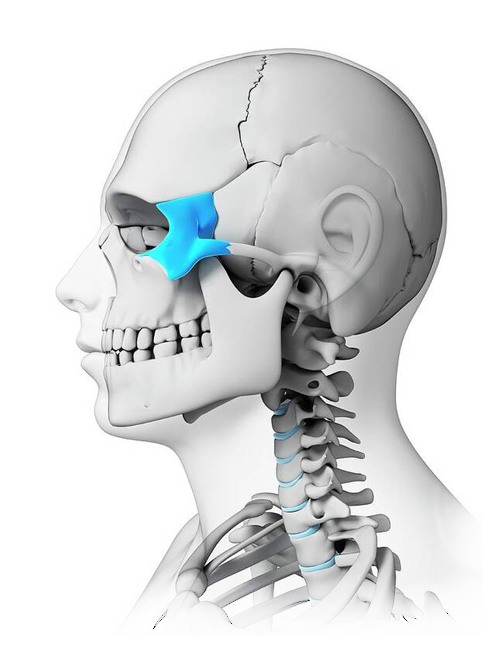

Zygomatic & Orbital Floor Implants

Indications:

- Orbital Floor Fractures (blowout fractures, comminuted floor defects).

- Zygomaticomaxillary Complex (ZMC) Fractures.

- Orbital Rim Reconstruction following trauma or tumor resection.

- Midfacial Defects due to benign or malignant tumor excision.

- Orbital Volume Restoration to re-establish symmetry and support soft tissue positioning